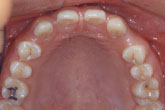

15세 7개월 된 남학생이 상악전치부 spacing을 주소로 내원하였다. 방사선사진을 촬영하고 상·하악 인상을 채득한 후 통상적인 방법으로 교정진단을 한 결과 다음과 같은 problem을 갖는 것으로 진단되었다 (그림 1,2).

그림 2. 내원시 측모두부방사선사진과 파노라마 사진을 통해 결손부위에 인접한 치아들의 위치를 파악할 수 있다.

측모두부방사선규격사진에서는 상악골이 다소 돌출되어 있는 양상을 보이고 있는 것 외에는 두드러진 문제가 보이지 않았다. 파노라마 사진에서 상악중철치의 치근이 짧은 것이 눈에 띄었으며 좌우 견치가, 특히 좌측 견치가 견치위치라기보다는 측절치 위치에 자리잡은 것으로 나타났다. 석고모형 분석 결과 상악의 공간 양은 약 16mm로 측정되었으며 개개 치아크기를 평균치와 비교시 상악 양 중철치가 두드러지게 작은 것을 알 수 있었다. 반면 하악은 정상적인 배열을 보였다. 상·하악 교합 분석시 좌측은 정상적인 Cl I을 보였으나 하악 치열 정중선의 우측 편위와 함께 우측교합은 Cl II를 나타내었다. OB과 OJ은 3.0과 3.5mm로 정상보다 1.0 또는 1.5mm 큰 양상을 보였다 (그림 2,3).